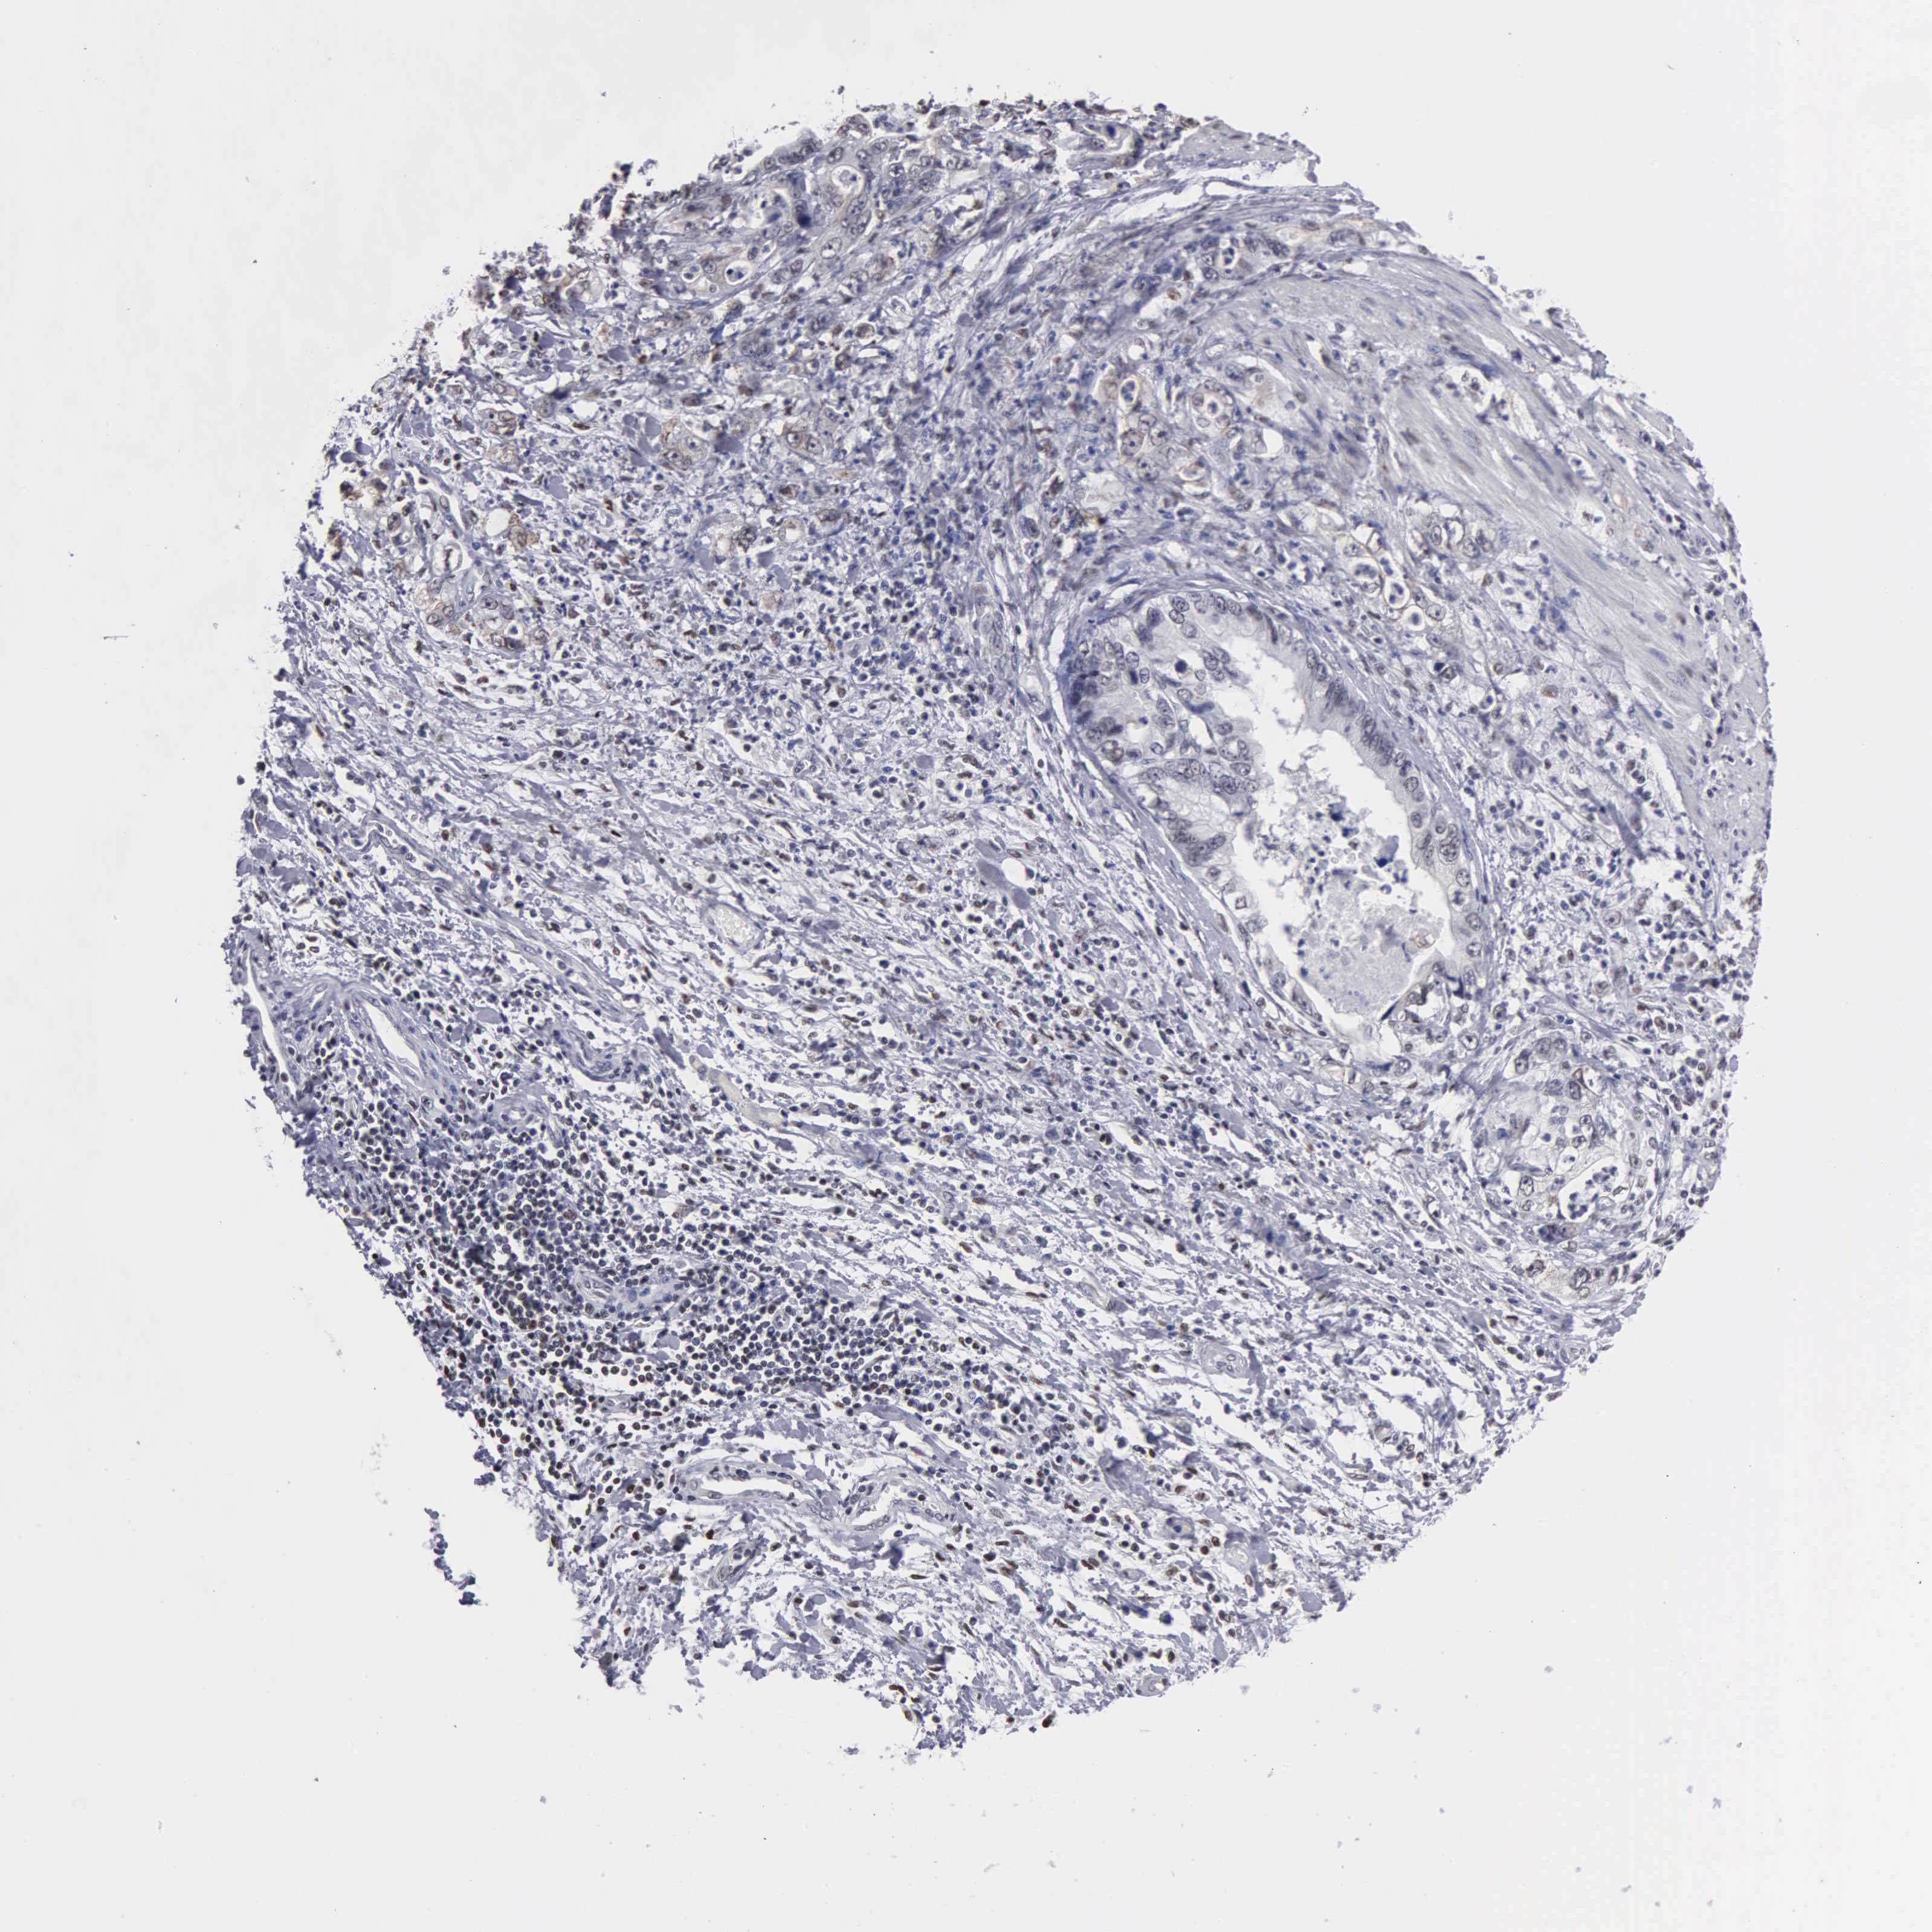

STOMACH CANCER - Protein expressioni

A mouse-over function shows sample information and annotation data. Click on an image to view it in a full screen mode. Samples can be filtered based on level of antibody staining by selecting one or several of the following categories: high, medium, low and not detected. The assay and annotation is described here.

Note that samples used for immunohistochemistry by the Human Protein Atlas do not correspond to samples in the TCGA dataset.

Antibody stainingi

Antibody staining in the annotated cell types in the current human tissue is reported as not detected, low, medium, or high, based on conventional immunohistochemistry profiling in selected tissues. This score is based on the combination of the staining intensity and fraction of stained cells.

Each image is clickable and will lead to virtual microscopy that enables deeper exploration of all samples and also displays staining intensity scores, fraction scores and subcellular localization as well as patient and tissue information for each sample.

Antibody CAB000350

Adenocarcinoma, NOS